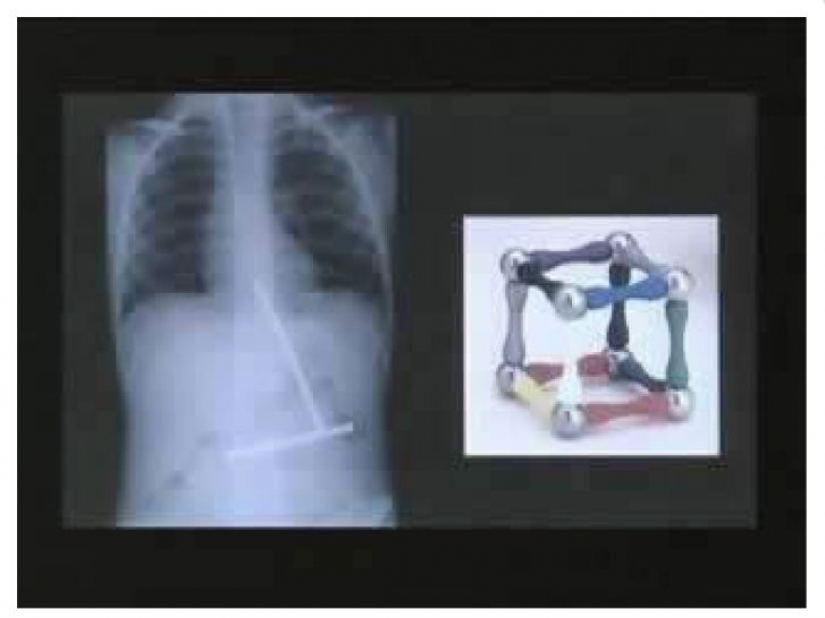

Un niño pequeño se comió un pedazo de juguete con el imán en un momento. Cuando finalmente todos los juguetes que estaban en el estómago del chico, se juntaron a una.